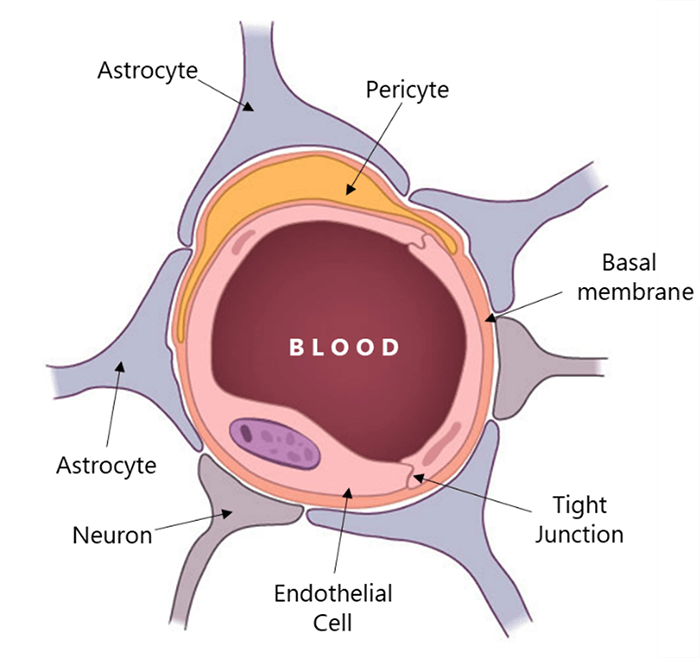

As the iodine-based contrast agents cannot cross the blood-brain barrier, the bolus exits most parts of the brain immediately after its arrival. This can be seen in cine-mode as a pattern of increasing and decreasing x-ray attenuation of each voxel, marking the arrival and departure of the contrast agent.

The instantaneous concentration of contrast material within each voxel is calculated by comparing the tissue attenuation at any time point with baseline images obtained before the arrival of the contrast bolus. Combining the measurements drawn from the several time points produces a concentration-versus-time curve (C1) for each voxel. Then a mathematical analysis of C1 for each voxel, generates a number of important parameters of hemodynamic performance, such as CBF, CBV, MTT, and the time-to-peak tissue response.